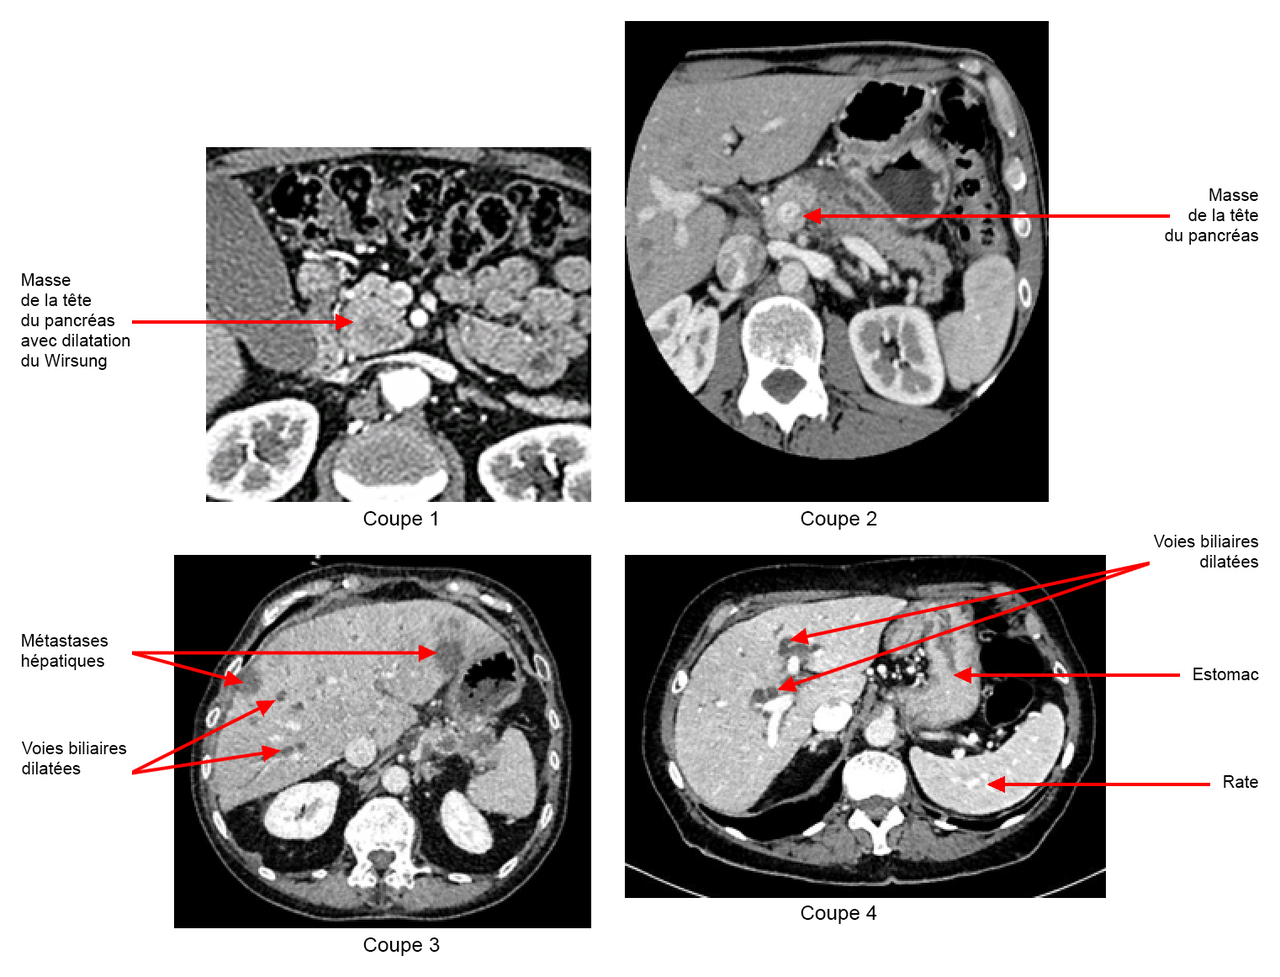

Vous recevez les résultats du bilan biologique : – hémoglobine (Hb) = 10,1 g/dL ; volume globulaire moyen (VGM) = 75 fl ; plaquettes = 550 G/L ; leucocytes = 18 G/L dont polynucléaires neutrophiles (PNN) à 15 G/L ; – natrémie = 136 mmol/L ; kaliémie = 3,4 mmol/L ; créatininémie = 70 umol/L ; – aspartate aminotransférase (ASAT) = 230 U/L (N < 30) ; alanine aminotransférase (ALAT) = 241 U/L (N < 30) ; gamma GT = 879 U/L (N < 60) ; phosphatases alcalines = 967 U/L (N < 100) ; bilirubine totale = 460 µmol/L (N < 17) ; bilirubine conjuguée = 400 µmol/L ; protéine C réactive (CRP) = 300 mg/L ; ferritine = 974 µg/L ; coefficient de saturation de la transferrine = 21 % ; taux de prothrombine (TP) = 45 %, facteur V = 98 %. Voici les coupes de scanner : Figure 1 (Source : Elisabeth Capelle, La Revue du Praticien)

Les hypodensités hépatiques sont probablement des métastases hépatiques, étant donné leur nombre, leur forme et surtout le contexte.

Figure 2 (Source : Elisabeth Capelle, La Revue du Praticien)

Vous faites donc le diagnostic d’angiocholite sur obstruction des voies biliaires par une tumeur de la tête du pancréas, associée à des images évocatrices de métastases hépatiques.